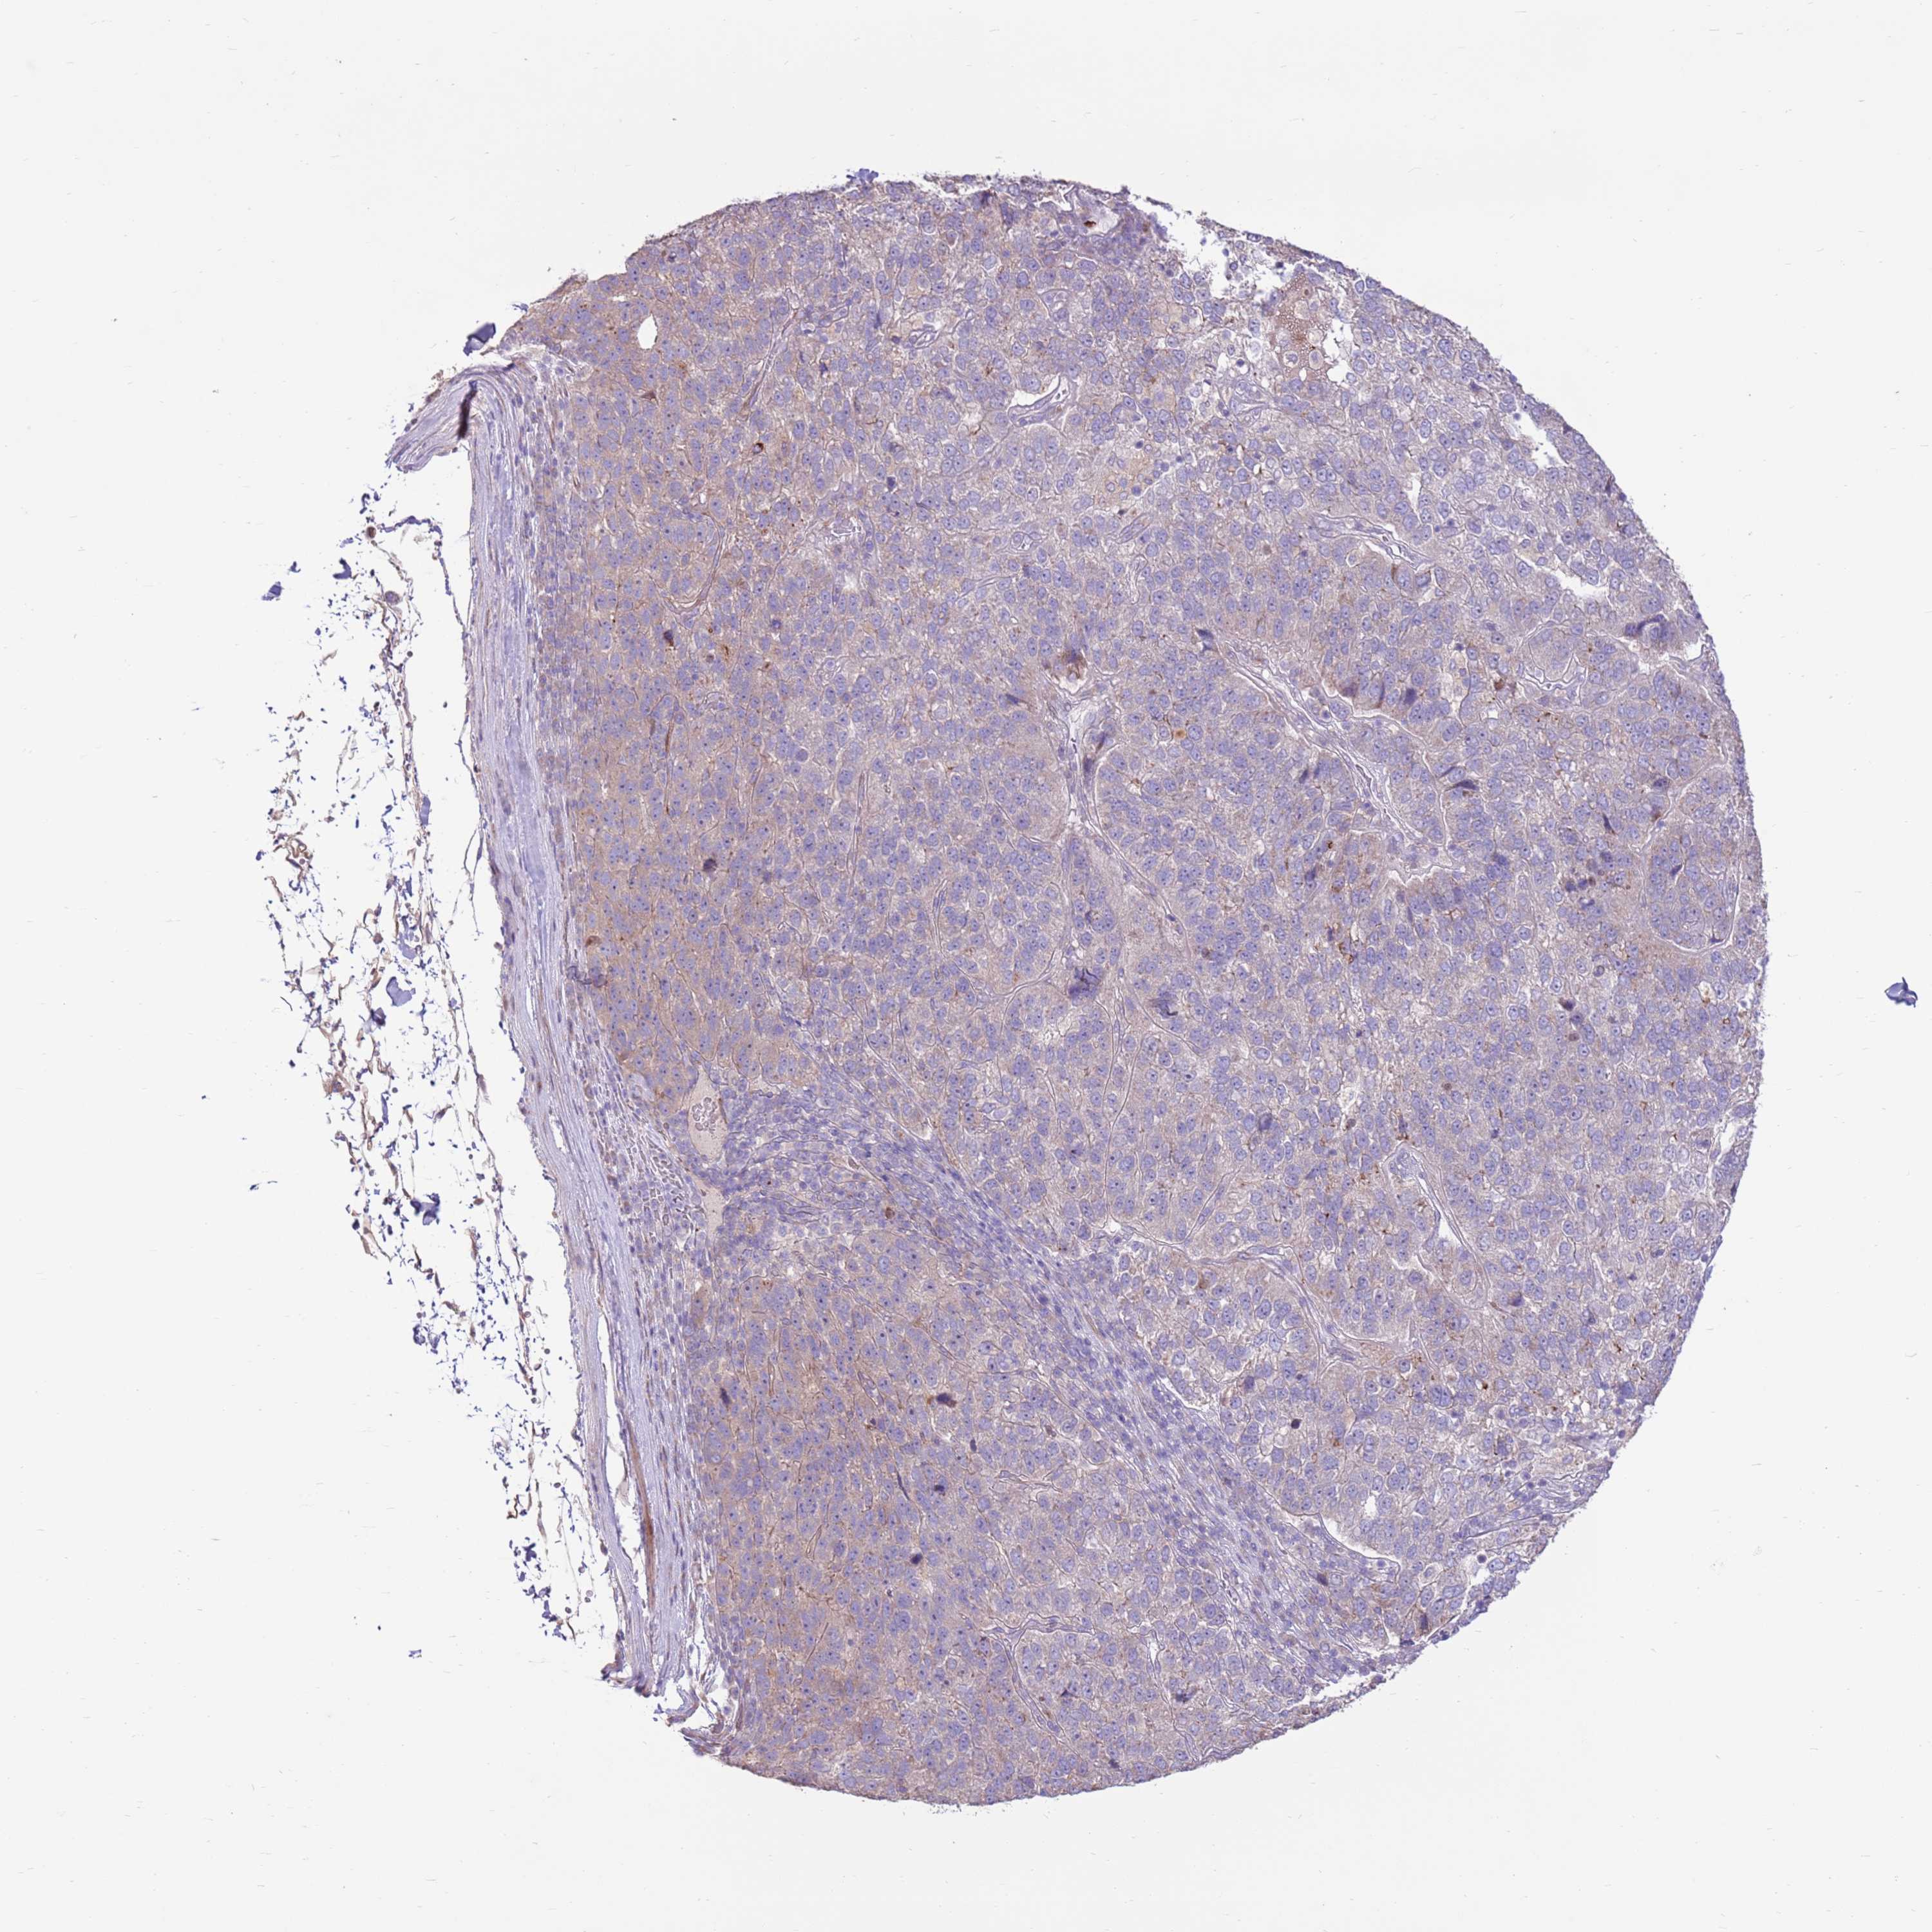

PANCREATIC CANCER - Protein expressioni

A mouse-over function shows sample information and annotation data. Click on an image to view it in a full screen mode. Samples can be filtered based on level of antibody staining by selecting one or several of the following categories: high, medium, low and not detected. The assay and annotation is described here.

Note that samples used for immunohistochemistry by the Human Protein Atlas do not correspond to samples in the TCGA dataset.

Antibody stainingi

Antibody staining in the annotated cell types in the current human tissue is reported as not detected, low, medium, or high, based on conventional immunohistochemistry profiling in selected tissues. This score is based on the combination of the staining intensity and fraction of stained cells.

Each image is clickable and will lead to virtual microscopy that enables deeper exploration of all samples and also displays staining intensity scores, fraction scores and subcellular localization as well as patient and tissue information for each sample.

Antibody HPA042116

Antibody HPA043556

Adenocarcinoma, NOS